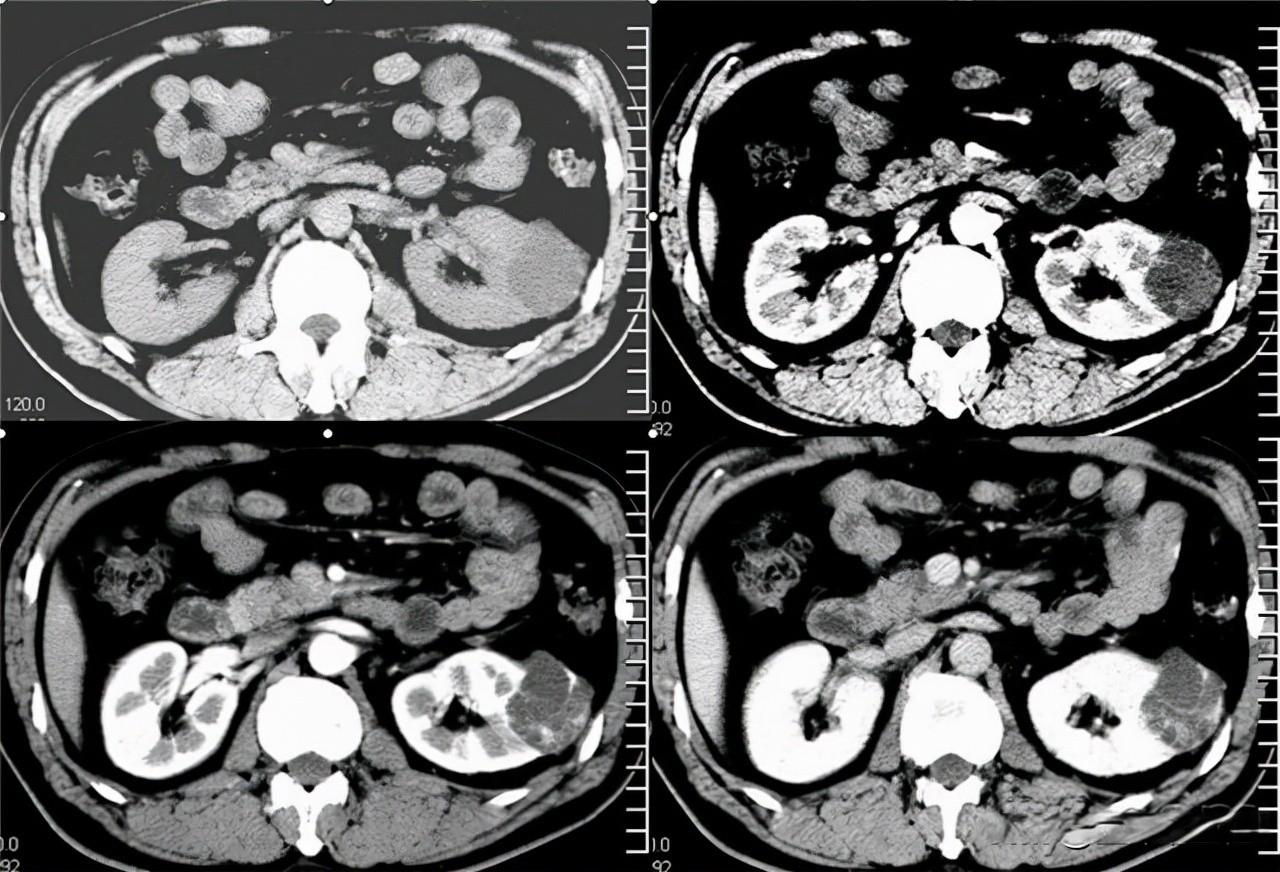

带着这些疑问,老张来到医院进一步检查。医生告诉他,肾囊肿是长在肾脏的一种囊状良性包块,通常是孤立的球形,可以是一个或多个,也可能只长在一侧肾脏或双肾都有。听到“良性”这个词,老张稍微松了口气。

老张今年55岁,得知这个数据后,他觉得自己并不是个例,心里又踏实了一些。医生接着说,单纯性肾囊肿一般都比较小,直径在0.5-2公分,囊壁薄而透明,囊内一般包裹着草黄色清亮的液体,是滤出的血浆成分。囊肿的生长往往比较缓慢,多数情况下人们都感觉不到任何不适的症状,多数都是在体检时偶然发现。